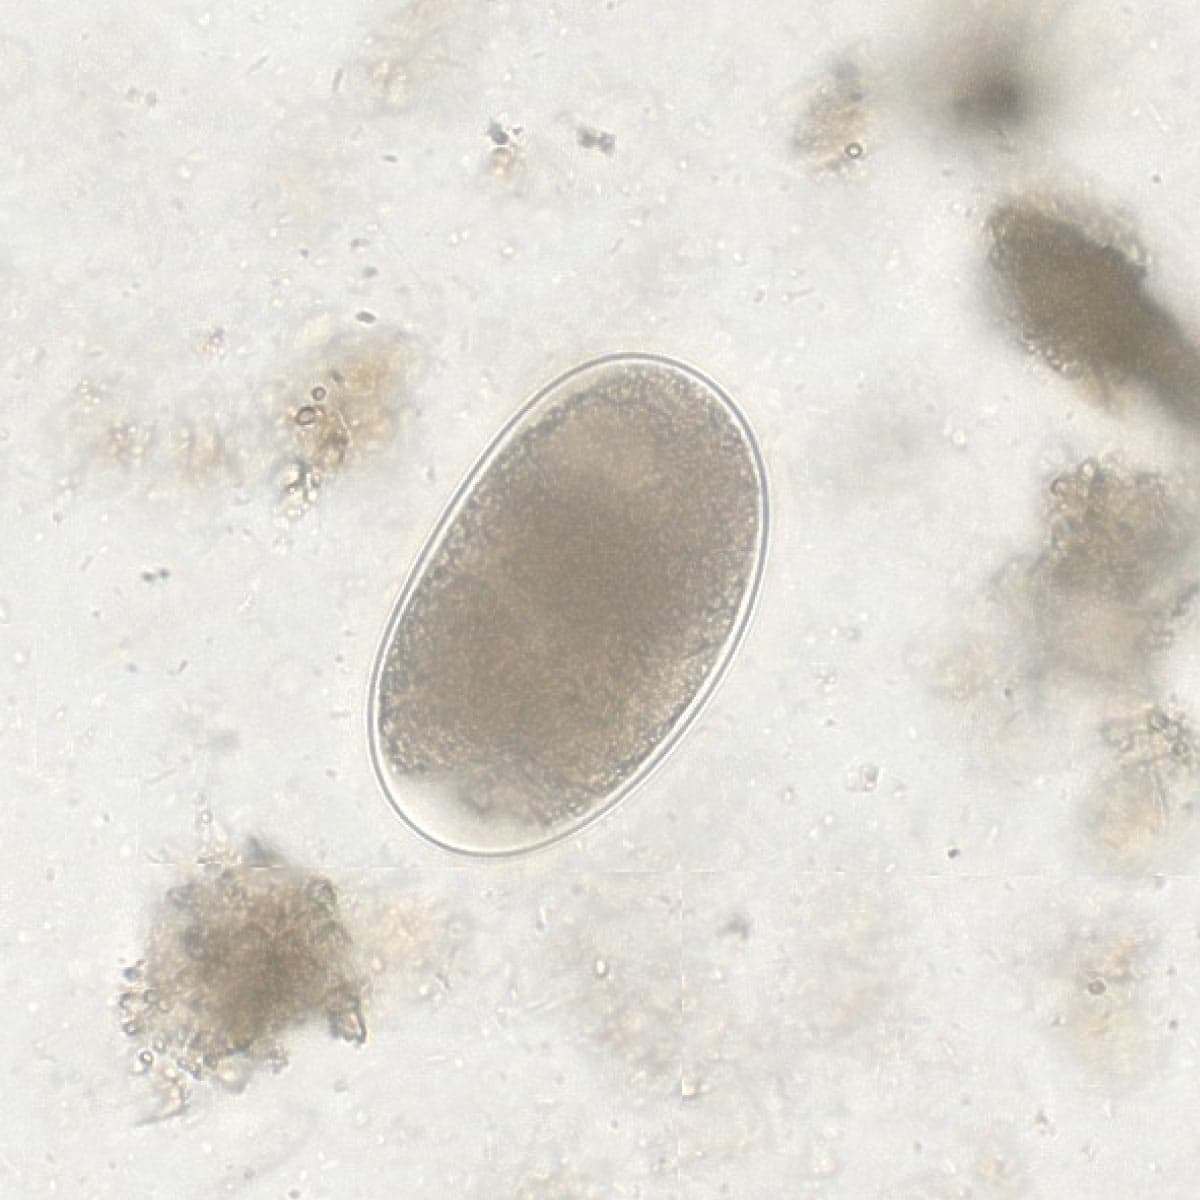

Once the data is uploaded, the AI instantly identifies parasite species. You receive visual evidence for every finding, with dimensions to confirm the identification. Simply review the AI’s results and provide the final diagnostic confirmation.